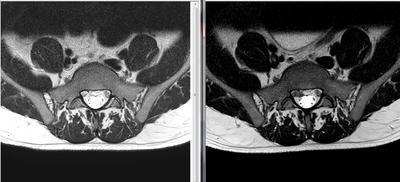

Not, i've done a NEW MRI (in the left is the MRI made in january, and in the right image is the MRI made in february 2016). The first was in january 2016, and this is february 2016.

The main difference in imaging is that the HDL got a little bigger, and also got to the point where the disc material got out and is "leaking" near the S1 right nerve root slightly compressing it.